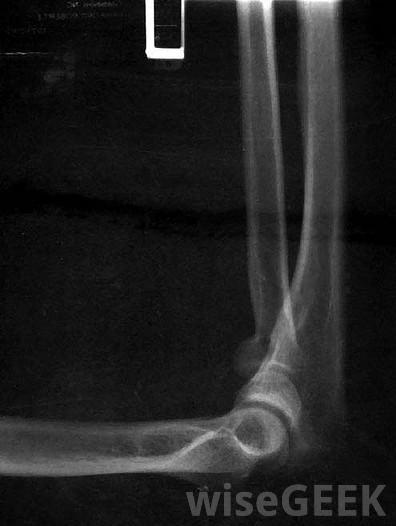

可能需要进行x光检查以确定肘部损伤的严重程度当你肘部骨折后去看医生,医生会给你做检查。在检查过程中,你可能要拍X光片,回答关于你受伤的问题以及受伤的原因,让医生测试你的手臂能移动多远。骨头完全断裂可能只需要夹板和休息。如果骨头严重受损或脱离正常位置,或者需要取出骨头碎片,手术可能是一个合适的治疗选择,医生会给你开什么样的治疗方案取决于你的年龄,你受到的损伤的类型,以及骨折后骨骼的位置